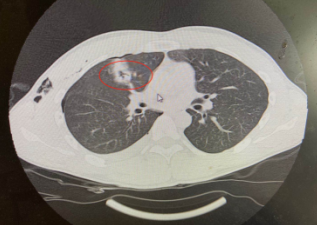

肺部戳洞

2020年3月29日,徐州丰县一男子在家干活时不慎从2米高的地方跌落,被约1.2米长的铁撬棍从肛门插入,插入长度约1米,当时家属帮助其拔出撬棍,并立刻拨打了120电话,前往我院接受治疗。急诊CT显示患者胸腹贯通伤、肛门开放性损伤、右肺贯通伤、右侧血气胸、直肠破裂等多处损伤,情况非常危险。普外科医生团队为其进行了6个小时手术,术后患者转入ICU,平稳度过危险期。